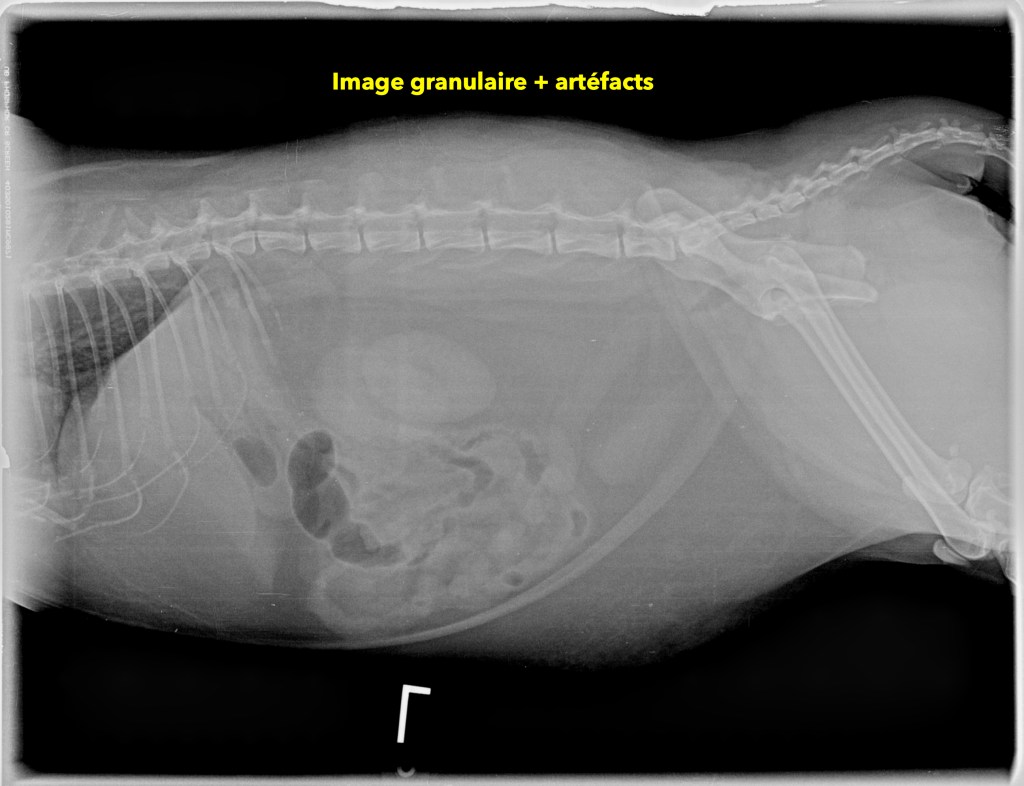

qualitecc81-3b_radio-artecc81facts-2